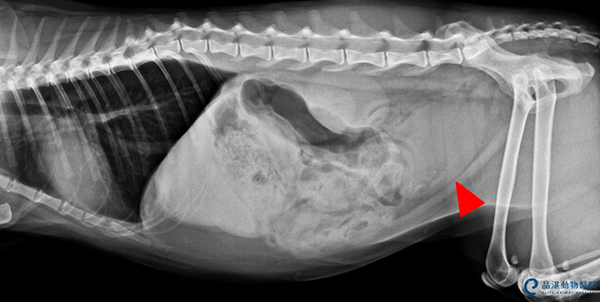

Fig 1 經X光檢查可發現膀胱有許多小細砂(紅色箭頭指示白色亮點處),導致尿道阻塞,無法排尿。